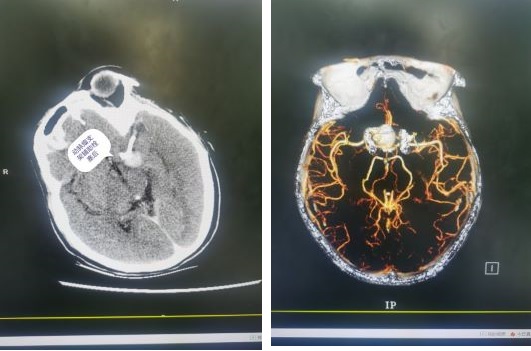

神经外科团队在询问患者病史后,初步判断她是脑血管出现了问题。根据患者的病史和影像学检查,诊断为:后交通巨大动脉瘤。动脉瘤形态不规则,随时可能破裂出血,严重者可造成生命危险。

第一师医院神经外科王和功主任、杨慧东副主任、刘俊医师等团队成员认真研究病情、反复探讨手术方案,并请曾经在第一师医院神经外科援疆两年的陈贤谊教授的指导下,为患者行密网支架(血流导向装置)植入术。

密网支架又被称为血流导向装置,它通过血流动力学机制起作用,通过改变进入动脉瘤的血流方向,从而达到彻底、持久的动脉瘤栓塞效果。另一方面,它提供血管内皮细胞攀爬生长的脚手架,促进内皮化修复,修复载瘤动脉结构的完整性。这相当于在血管和动脉瘤瘤颈交界处“筑”起了一面墙,把动脉瘤隔绝在血管外,从而使这颗不定时“炸弹”失效,有效防止动脉瘤复发及破裂。功夫不负有心人,经过陈贤谊、王和功和杨慧东的缜密操作,手术顺利完成,动脉瘤被成功拆除!